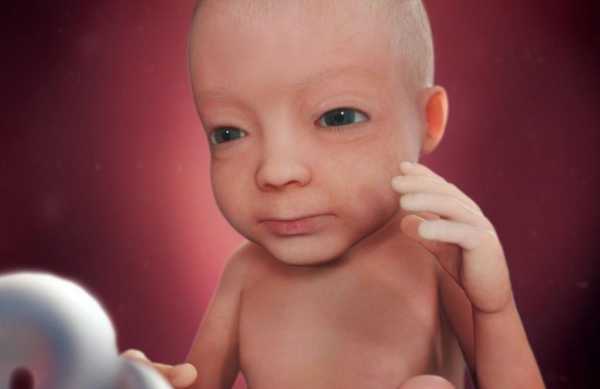

Пропорции тела ребенка аналогичны пропорциям новорожденного. Вес ребенка на 27 неделе беременности составляет 800-900 г, а рост около 32-33 см. Длина стопы вашего малыша может достигать 2 см. Чтобы легче было представить, малыш напоминает по размерам фрукт помело или школьный глобус.

Кожа малыша еще очень тонкая и сморщенная, так как он находится в водной среде. А пушковые волосы на теле начинают темнеть. Наступает и решающая стадия в развитии коры головного мозга. Нейронные связи становятся более активными и готовят почву для полноценного развития ребенка после его появления на свет. Благодаря этому, у ребенка продолжают закладываться режимы сна и отдыха. И уже сейчас ваш малыш ведет себя, как новорожденный, он может засыпать и просыпаться в определенное время и подолгу играть с пуповиной или своими конечностями.

Основные черты личика вашего малыша уже сформировались, теперь он будет набираться сил и готовиться к предстоящим родам. Глаза вашего крохи уже открыты, он может моргать с определенным интервалом и видеть свет через стенку живота. Ваш малыш уже более осознанно может двигать своими ручками и ножками. Он может с интересом наблюдать, как сжимаются и разжимаются его пальчики, и класть их в рот.

Вес ребенка на 27 неделе равен 900 граммам, а его рост составляет 30-35 см. Ребенок спит почти 20 часов в сутки, но часто просыпается, чтобы перевернуться и передать привет маме.

На 27 неделе беременности мамочкам всегда интересно знать, что же происходит с их долгожданным плодом. Можно отметить несколько основных моментов.

- Вес малыша около 1 кг, а рост примерно 35 см.

- С каждым днем малютка становится все симпатичнее. Его жировая прослойка утолщается, складки на теле пропадают. Если на 27 неделе сделать УЗИ, то фото малыша отразит эти изменения.

- Глаза уже приоткрыты, а реакция на свет острее. Если направить на живот яркий свет, малыш повернется.

- Кроха может надувать щеки, сжимать кулачки.

- Ребенок чувствует боль, совершенствует умение сосать и глотать.

- Активно развивается область мозга, ответственная за мышление и сознание.

Что происходит с плодом за пару месяцев до ожидаемых родов? Ребенок достигает «внушительных» размеров: он весит от 800 до 1000 г, а его рост равняется примерно 35-38 см. Вес плода в 27 недель беременности может быть и чуть больше и немного меньше, все зависит от индивидуальных особенностей. Расположен плод может быть как головкой, так и ножками вниз: он еще до конца не «определился» со своим положением.

К этому времени малыш становится похож на новорожденного. Его тело пропорционально, но еще худое. С этой недели подкожный жир только начинает запасаться. Поэтому скоро эпителий не будет выглядеть сморщенным и кожа станет белее гладкой.

К этому времени малыш становится похож на новорожденного. Его тело пропорционально, но еще худое. С этой недели подкожный жир только начинает запасаться. Поэтому скоро эпителий не будет выглядеть сморщенным и кожа станет белее гладкой.

Пушковые волосы темнеют, начинают развиваться волосяные фолликулы. Личико полностью сформировано, на нем можно различить индивидуальные черты. В этот период не развиты только щечки.

В среднем на сроке 27 недель рост плода составляет около 35 см и более, вес достигает 1000 г. Его ножки скрещены, а ручки прижаты к груди. Что, однако, не мешает ему переворачиваться – места в матке для свободных движений еще достаточно. Эти упражнения становятся все ощутимее и заметнее внешне, когда на животе беременной выпирает ладошка или маленькая пятка. На этом сроке малыш обычно занимает положение головой вниз, в котором остается до момента рождения.

Вот так выглядит плод на двадцать седьмой неделе:

Полный рост плода составляет примерно 34 см (от макушки до пяточек) вес около 1 кг.

Плод продолжает набирать массу, необходимую для жизни вне утробы матери. К концу шестого акушерского месяца вес малыша достигает отметки в 850-950 грамм. Рост будущего ребенка увеличивается не так быстро, на двадцать седьмой неделе беременности он составляет 34 сантиметра.

Лицо малыша приобретает черты взрослого человека. У ребенка уже имеются оформленные глаза, губы, ноздри. К началу третьего триместра у плода наблюдается развитие хрящей носа и наружного уха, малыш имеет реснички и брови.

К концу шестого акушерского месяца тело будущего ребенка становится все более похожим на новорожденного. Мальчики и девочки имеют сформированные наружные половые органы. На кожном покрове все еще находятся пушковые волосы, которые к концу третьего триместра начинают темнеть.

Верхний слой эпидермиса сморщен, но наблюдается его постепенное расправление. Окраска кожи сменяется с ярко-красного цвета на розоватый оттенок. На данном сроке начинается активное отложение жировой клетчатки под дермой.